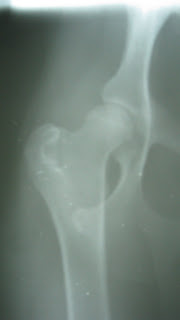

Is this a good hip???

Yikes!! If you didn't know the history on this little pup you would think he must have had some form of trauma and dislocated his hip. Unfortunately, both of his hips look like this, they are both dysplastic. He is a small breed dog about 10-12 pounds and around one year of age. He presented for dislocating knee caps (patellar luxation) and in the preliminary xrays for knee surgery we always evaluate the hip/knee alignment. Good thing, because we had no idea this little guy had "floating" hips. If he develops pain as he gets older, he is too small for a conventional total hip joint replacement and he will get an FHO (Femoral Head and Neck Ostectomy) to alleviate any discomfort. This owner is potentially anticipating 4 orthopedic surgeries in this little guy, both hips and both knees. What an investment! It is always sad to give owners this type of news and shows us that good breeding is best for the pet and the owner.

Good Hip, Bad Hip

Can you tell the difference between these two hip radiographs? Hip Dysplasia is a devastating disease for many dogs. Hips can be degenerative as early as age 1 to 2 years of age. The way to evaluate for this disease is done by taking survey radiographs (x-rays) in a specific position. Breeding dogs should be screened for this disease prior to breeding, if either potential parent is dysplastic they should not be bred, no exceptions. However, occasionally two normal adult dogs may still have puppies with dysplasia, but it is much less likely. Dogs that are diagnosed with Hip Dysplasia have options for surgery or medical treatment. If the problem is detected prior to 8-10 months of age a surgery called a TPO (Triple Pelvic Osteotomy) can be performed to improve the joint conformation so that arthritis does not set in. If the dog is over 10-12 months, or if degeneration is already present they may be managed medically for a while and tend to do better if not overweight. Later they may be a candidate for a THR (Total Hip Replacement). The cost of these surgeries are ranging from $1,800.00 to $4,500.00. If left untreated the hip typically begins to separate from the joint socket and causes pain, stiffness and the inability to get up from a sitting or laying position. Late in the disease we occasionally see dogs that cannot even get up anymore or when walking their hips dislocate and they fall. Eventually there may be a genetic marker for this disease which would help us try to eliminate dysplasia and other genetic diseases from the dog population with a blood test. High risk breeds are large and giant breed dogs. (St. Bernards, Great Danes, Mastiff, Labradors etc...) OFA (Orthopedic Foundation for Animals) is an organization that screens and certifies hips, elbows, eyes, cardiac disease and other specific genetic conditions in many breeds. You can visit their website for more information at www.offa.org